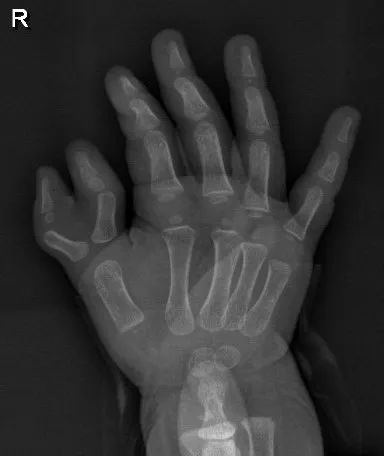

10个月宝宝右手有六指广州医生手术成功为他切除了多指